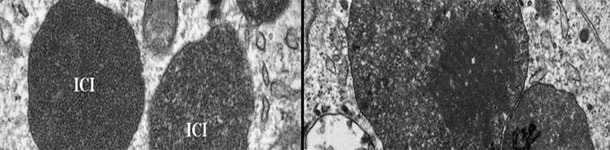

Electron micrograph of a lymph node from a PCV2-SD affected pig. Note the presence of PCV2 intracytoplasmic inclusion bodies (ICI); in some areas, the viral particles can be arranged in paracristalline arrays (inset of the right image). Picture courtesy of Carolina Rodríguez-Cariño, PhD thesis.